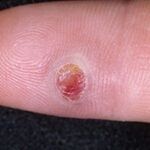

Lymphangioma circumscriptum, the common form of cutaneous lymphangioma, is characterized by persistent, multiple clusters of translucent vesicles that usually contain clear lymph fluid (often compared to frog spawn). These vesicles represent superficial saccular dilations from underlying lymphatic vessels that occupy the papilla and push upward against the overlying epidermis. Each skin lesion may range from a minute vesicle to a small bulla-sized lesion. These vesicles can be clear or vary from pink to dark red because of serosanguineous fluid and hemorrhage. These vesicles often are associated with verrucous changes, which give them a warty appearance.

- Lymphangioma circumscriptum involves small clusters of vesicles measuring about 2-4 mm. These clear vesicles can vary from pink to red to black secondary to hemorrhage.

- The lesions can have a warty appearance on their surface; as a result, these lesions are often confused with warts.